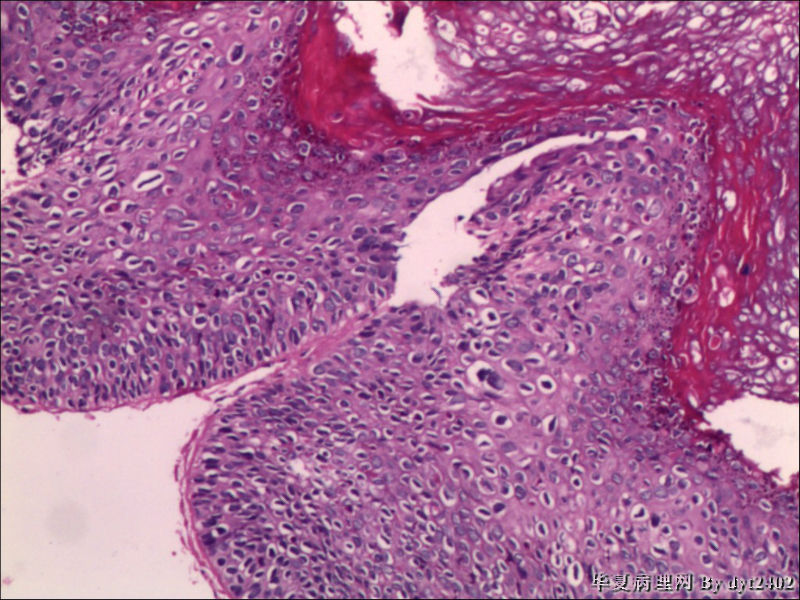

这样的外阴病变 发个原位癌是否合适?

• 这样的外阴病变 发个原位癌是否合适?图1

图1

原位癌够了,不排除其他地方有浸润。

似乎有浸润了

VIN III,做个银染或者标个免疫组化看一下基底膜是否完整。

VIN III